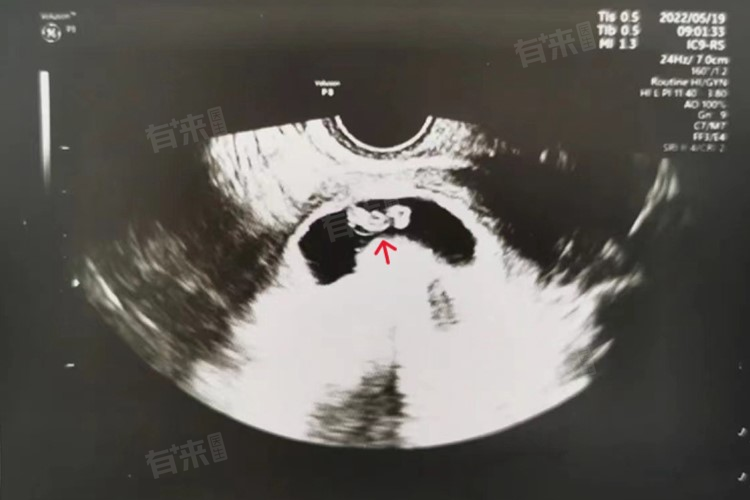

怀孕45天未见胎心胎芽是比较正常的情况。一般来说,怀孕后胚胎的发育是一个渐进的过程,正常情况下,在怀孕后的5-6周可以通过超声检查看到胎芽,而胎心通常在怀孕后的6-7周出现。但这只是一个大致的时间范围,实际的出现时间会因多种因素而有所不同。

1、超声检查:主要用于确定孕囊位置、大小、形态,判断是否为宫内妊娠,并观察胚胎的发育情况。